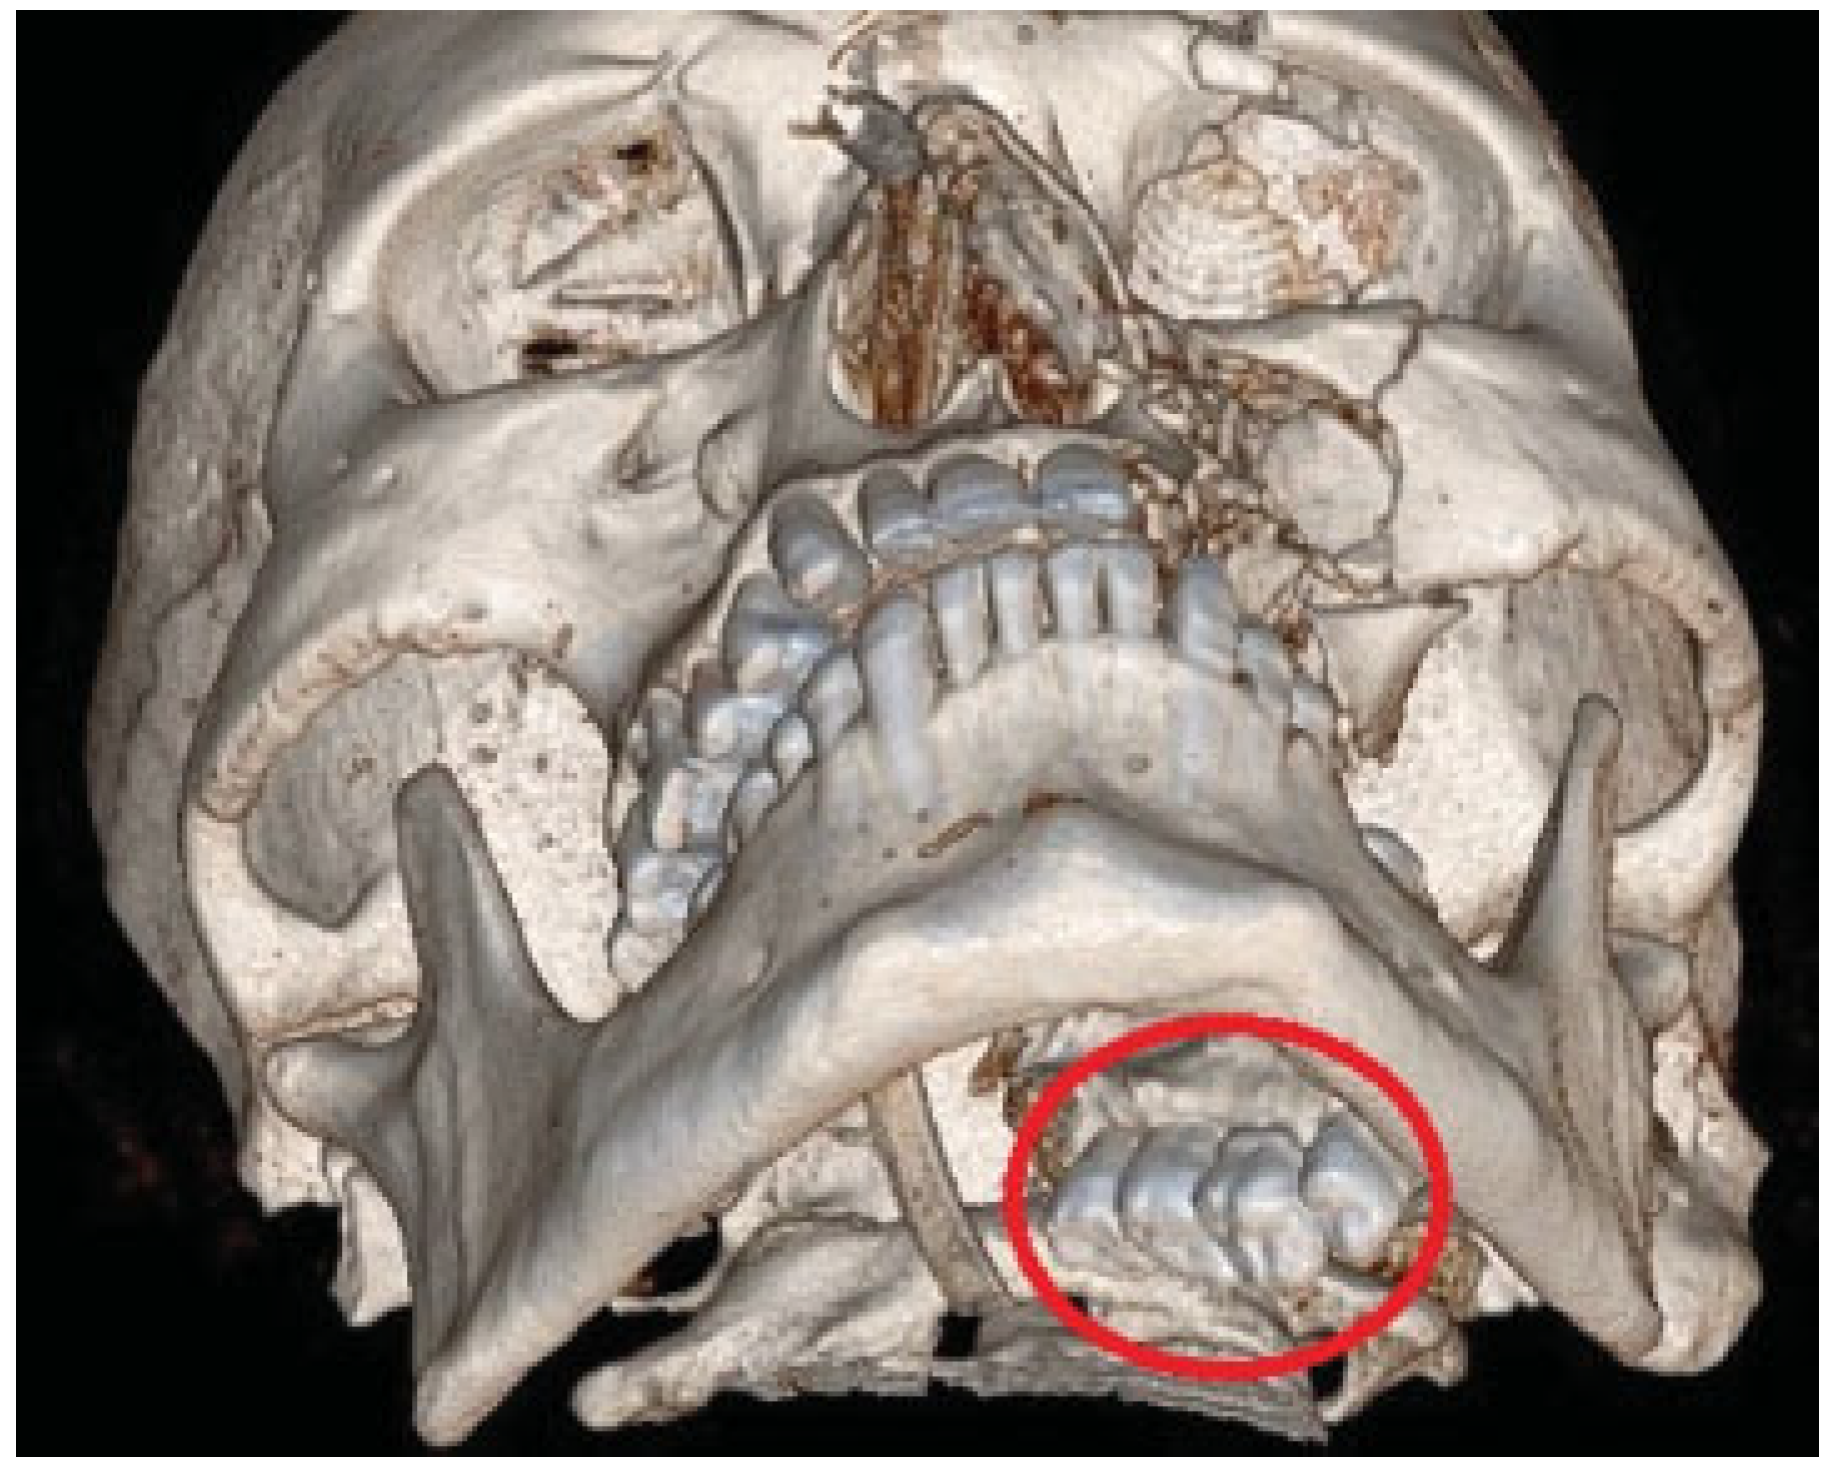

Figure 2.

3D computed tomography scan showing displacement of fractured maxillary segment into lateral pharyngeal space.